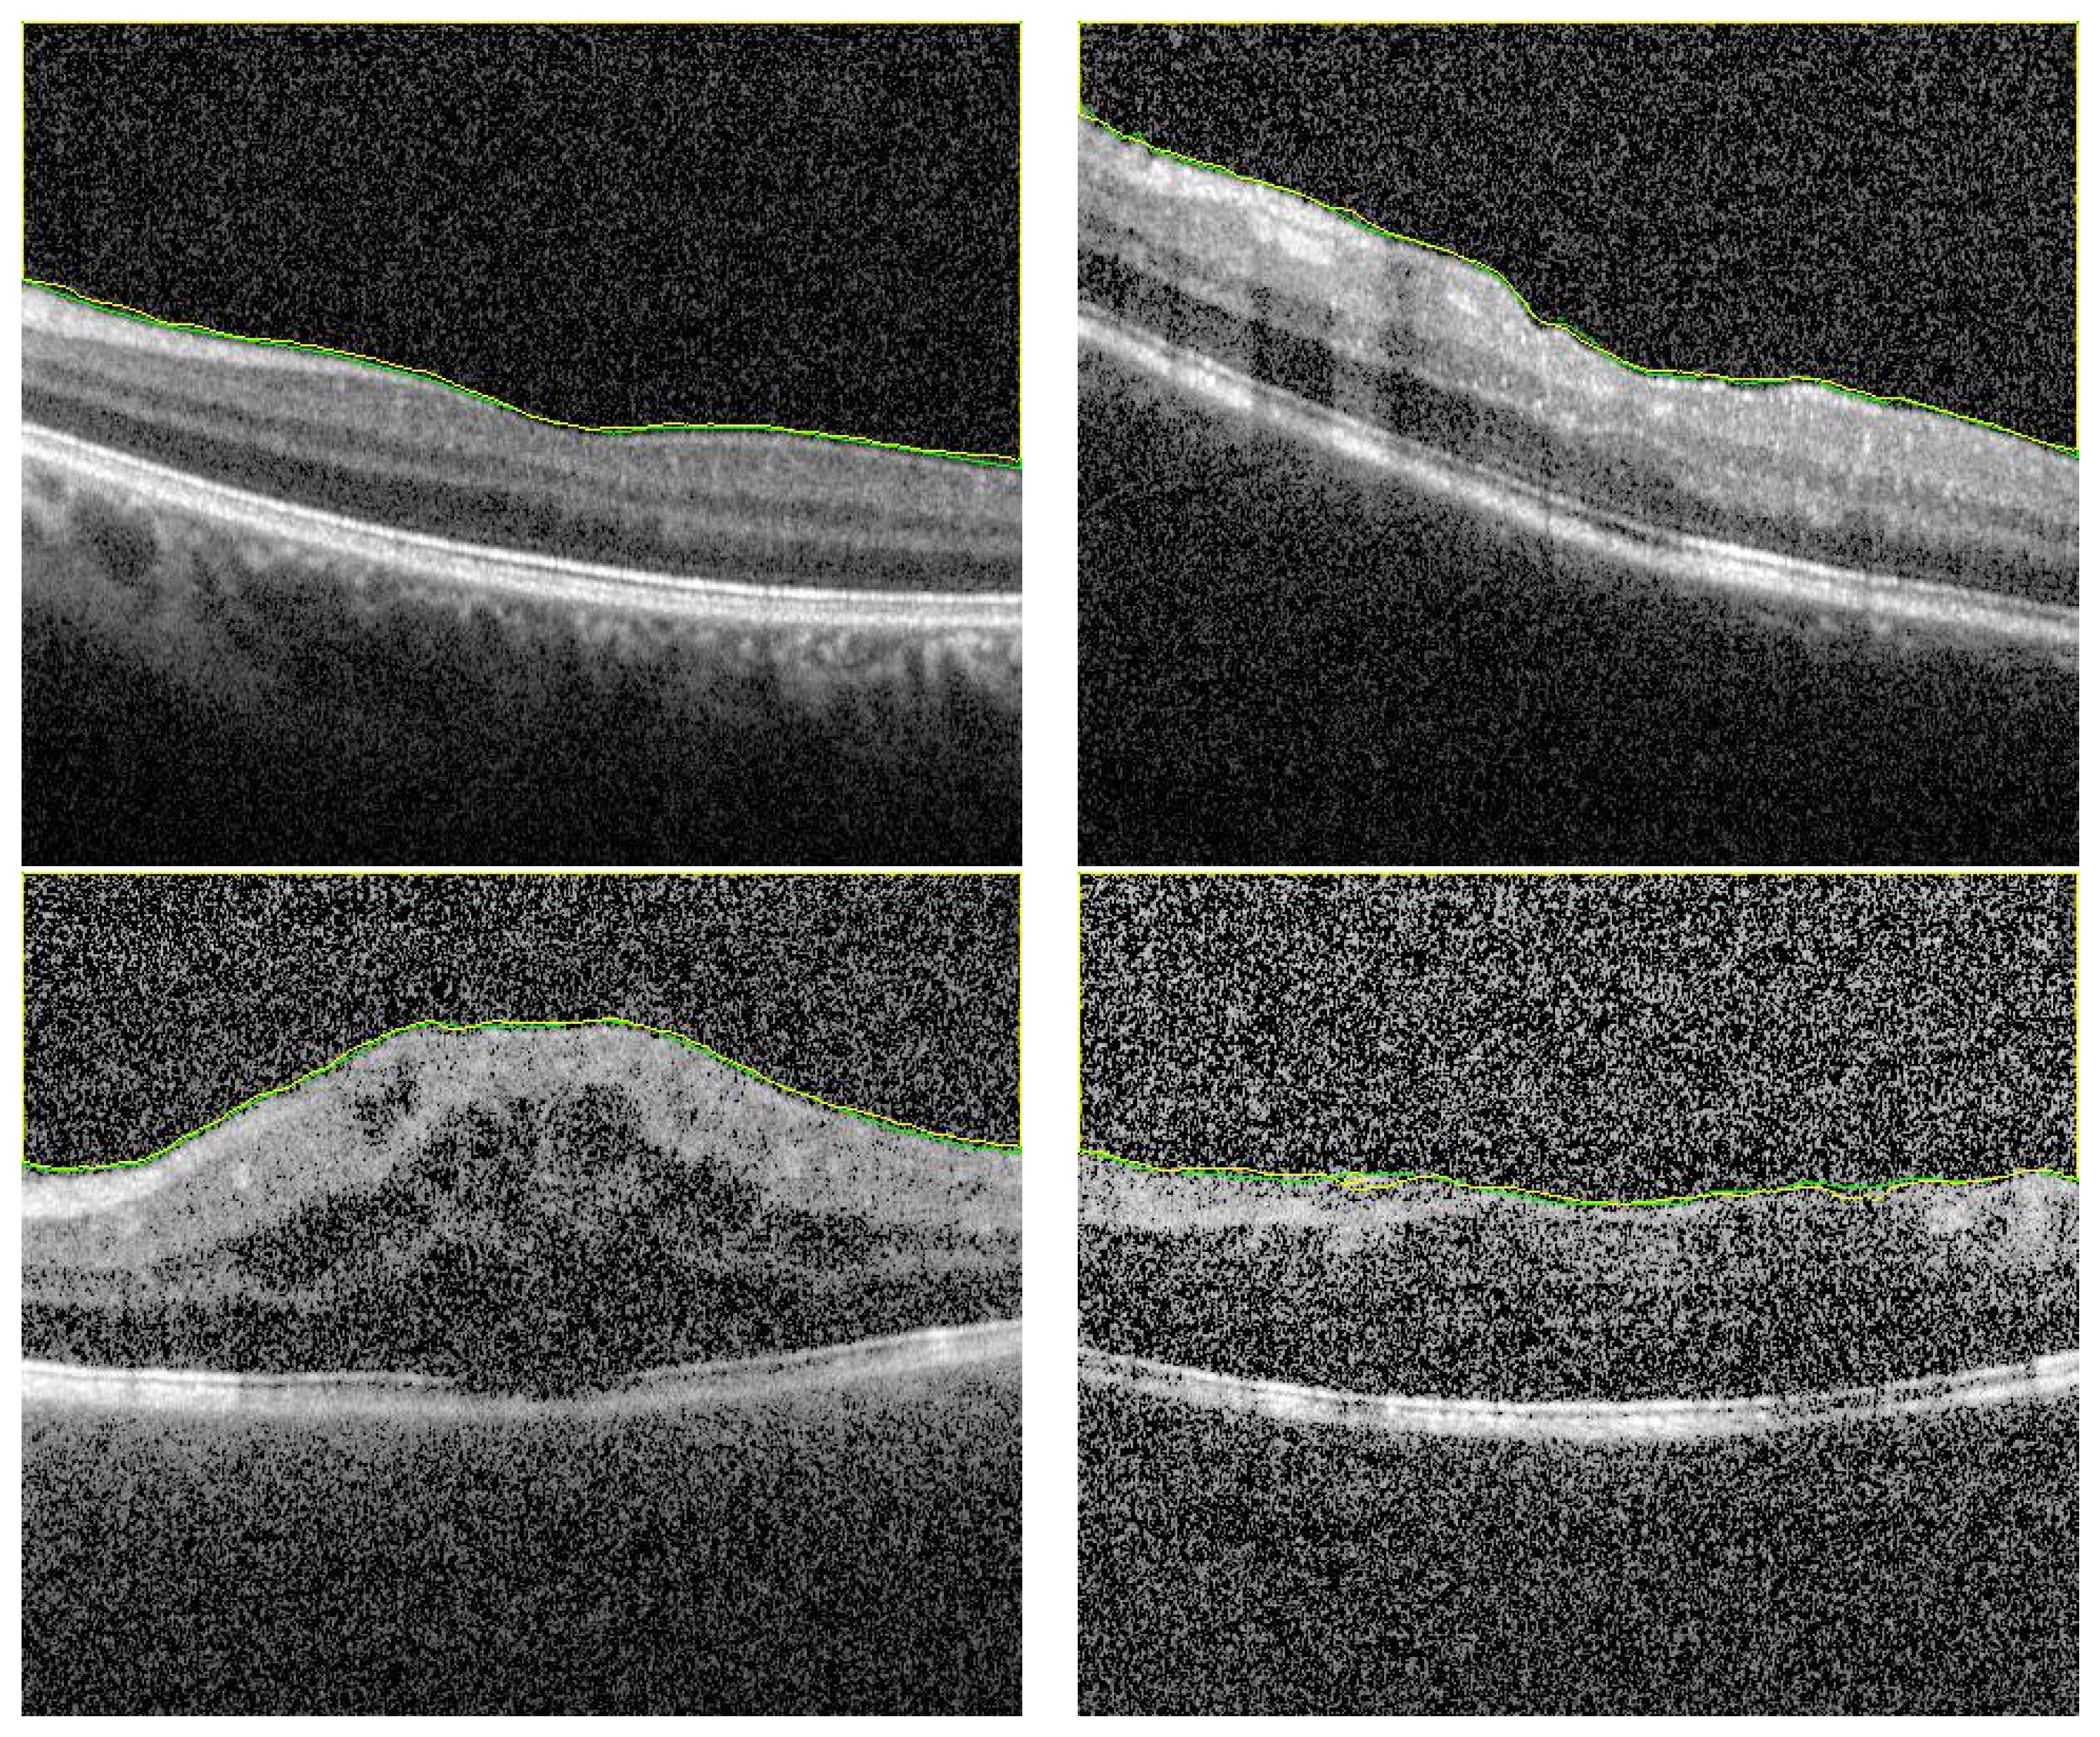

3.3. Overall Segmentation Evaluation

3.4. Ablation Study